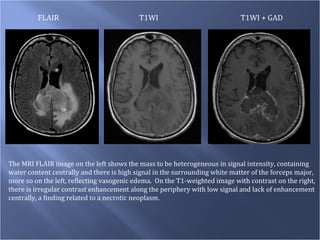

FLAIR T1WI T1WI + GAD The MRI FLAIR image on the left shows the mass to be heterogeneous in signal intensity, containing water content centrally and there is high signal in the surrounding white matter of the forceps major, more so on the left, reflecting vasogenic edema.  On the T1-weighted image with contrast on the right, there is irregular contrast enhancement along the periphery with low signal and lack of enhancement centrally, a finding related to a necrotic neoplasm.

FLAIR T1WI T1WI+ GAD The MRI FLAIR image on the left shows the mass to be heterogeneous in signal intensity, containing water content centrally and there is high signal in the surrounding white matter of the forceps major, more so on the left, reflecting vasogenic edema. On the T1-weighted image with contrast on the right, there is irregular contrast enhancement along the periphery with low signal and lack of enhancement centrally, a finding related to a necrotic neoplasm.